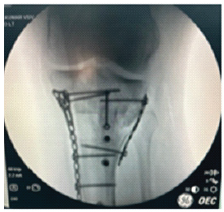

Single-Stage Correction of Genu Recurvatum with Dual-Pillar Plating – A Case Report

V S V Kumar , Velmurugan Srinivasan , S N Muthu Adaikkappan , S Rajasekar , A S Hemapriya

………………………………p.36-43